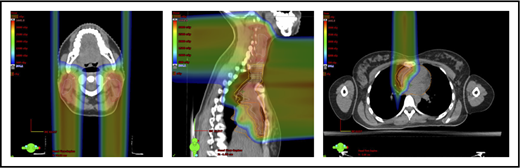

Scans for a young woman in whom the target included mediastinal, left parasternal, and left axillary regions. One anterior field was used for the mediastinum, and a separate posterior field was used for the axillary region.

With regard to field arrangements, the PBSPT technique for an anterior upper mediastinal and lower neck target usually requires 1 (repainted) or 2 anterior fields. For more complex target volumes, targets can be divided into 2 or more parts (eg, neck CTV, mediastinal CTV, and axillary CTV), and a multifield plan can be used (Figure 5). For cases that involve lower (posterior) and upper (anterior) mediastinal targets, a combination of posterior and anterior fields can maximally spare the heart and lungs (Figure 6). For upper neck targets, lateral or posterior fields can avoid the oral cavity/salivary structures. For axillary targets, a posterior field can help to spare breast tissue. Although these various field arrangements can be used in PSPT, gradient matching is simpler in PBSPT when the fields overlap or oppose, obviating the need for feathering.